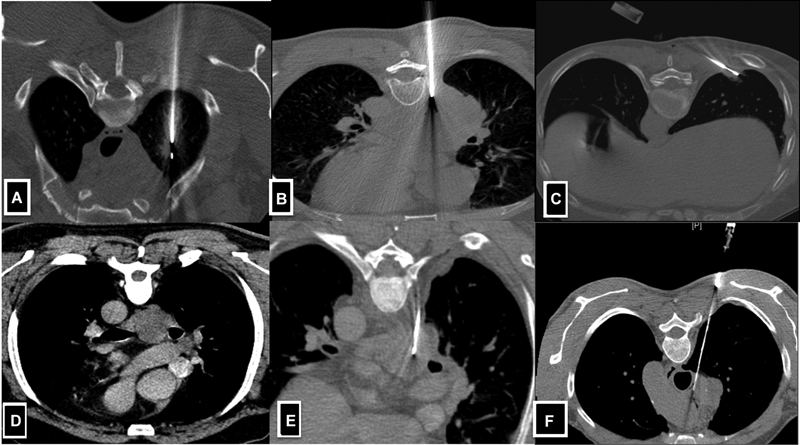

A)Diagnosis of pulmonary nodules-computed tomography (CT) is the preferred image guidance modality. Ideally, the most vertical (perpendicuar) path is selected, which avoids bullae, interlobar fissures, and large vessels[5] ([Fig. 1A–C]).

B)Mediastinal lesions-CT-guided direct mediastinal or extrapleural approach is generally preferred over a transpulmonary approach to avoid pleural transgression and thereby decrease the risk of pneumothorax and pulmonary haemorrhage.[6] Ultrasonographic (USG) guidance can be used for large mediastinal lesions, which are in contact with the chest wall and are easily visualised ([Fig. 1D–F]).

| Fig 1 :(A-F) Axial CT images demonstrate lung and mediastinal lesion biopsy technique. A-Solitary lesion in the right upper lobe posterior approach taken where the needle is perpendicular to the lesion. B-Large lung mass in the right lower lobe posterior approach taken for biopsy. C-Small lesion located in the subpleural location of the right lower lobe, tangential approach taken to obtain the larger length of the core. D & E-CECT reveals subcarinal lymph node in k/c/o carcinoma of the lung. Extrapleural posterior approach was taken with hydro dissection of the parietal and visceral pleural and a biopsy of the mediastinal lymph node was done.

| Fig 1 :(A-F) Axial CT images demonstrate lung and mediastinal lesion biopsy technique. A-Solitary lesion in the right upper lobe posterior approach taken where the needle is perpendicular to the lesion. B-Large lung mass in the right lower lobe posterior approach taken for biopsy. C-Small lesion located in the subpleural location of the right lower lobe, tangential approach taken to obtain the larger length of the core. D & E-CECT reveals subcarinal lymph node in k/c/o carcinoma of the lung. Extrapleural posterior approach was taken with hydro dissection of the parietal and visceral pleural and a biopsy of the mediastinal lymph node was done.